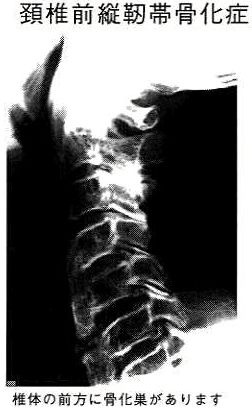

前縦靭帯骨化症/特定疾患情報

前縦靱帯骨化症とは後縦靭帯と対をなす靱帯で脊椎の前方を縦に走る前縦靱帯が骨化した状態を言います。これ自体が単独で症状を来し、治療の対象になることは稀です。わが国ではフォレステイル病とも呼ばれています。また強直性脊椎肥厚症と呼ばれることもあり、この病気との鑑別が困難なことがあります。